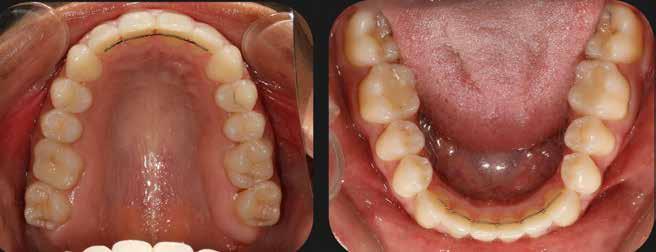

A 28 éves hölgypáciens is elsősorban a szép mosoly elérésének igénye miatt szeretett volna fogszabályozást, bár tudomása volt a mélyharapásáról (1–5. képek).

A kezelési célokat a fogívek tágítása a megfelelő mosolyszélességhez és az alsó frontfogak torlódásának feloldásához, valamint a mélyharapás és a kismértékű disztálharapás korrekciója jelentették (6–11. képek).

Passzív önligírozó fix fogszabá-

lyozó készülékkel 15 hónapig tartott a kezelése. Az ilyen mélyharapásos esetekben nagyon fontos, hogy a harapásemelésnél nem történik intrúzió a felső fogíven, mert az kifejezetten negatívan befolyásolná a vertikális mosoly-display-t! A fogszabályozó kezelés után, ahogy az általában lenni szokott, a bölcsességfogak eltávolításra kerültek. Mint minden esetben, a fogszabályozás aktív fázisa után a retenció, a passzív helyben tartó fázis a kezelési eredmény megtartásához rendkívül fontos!